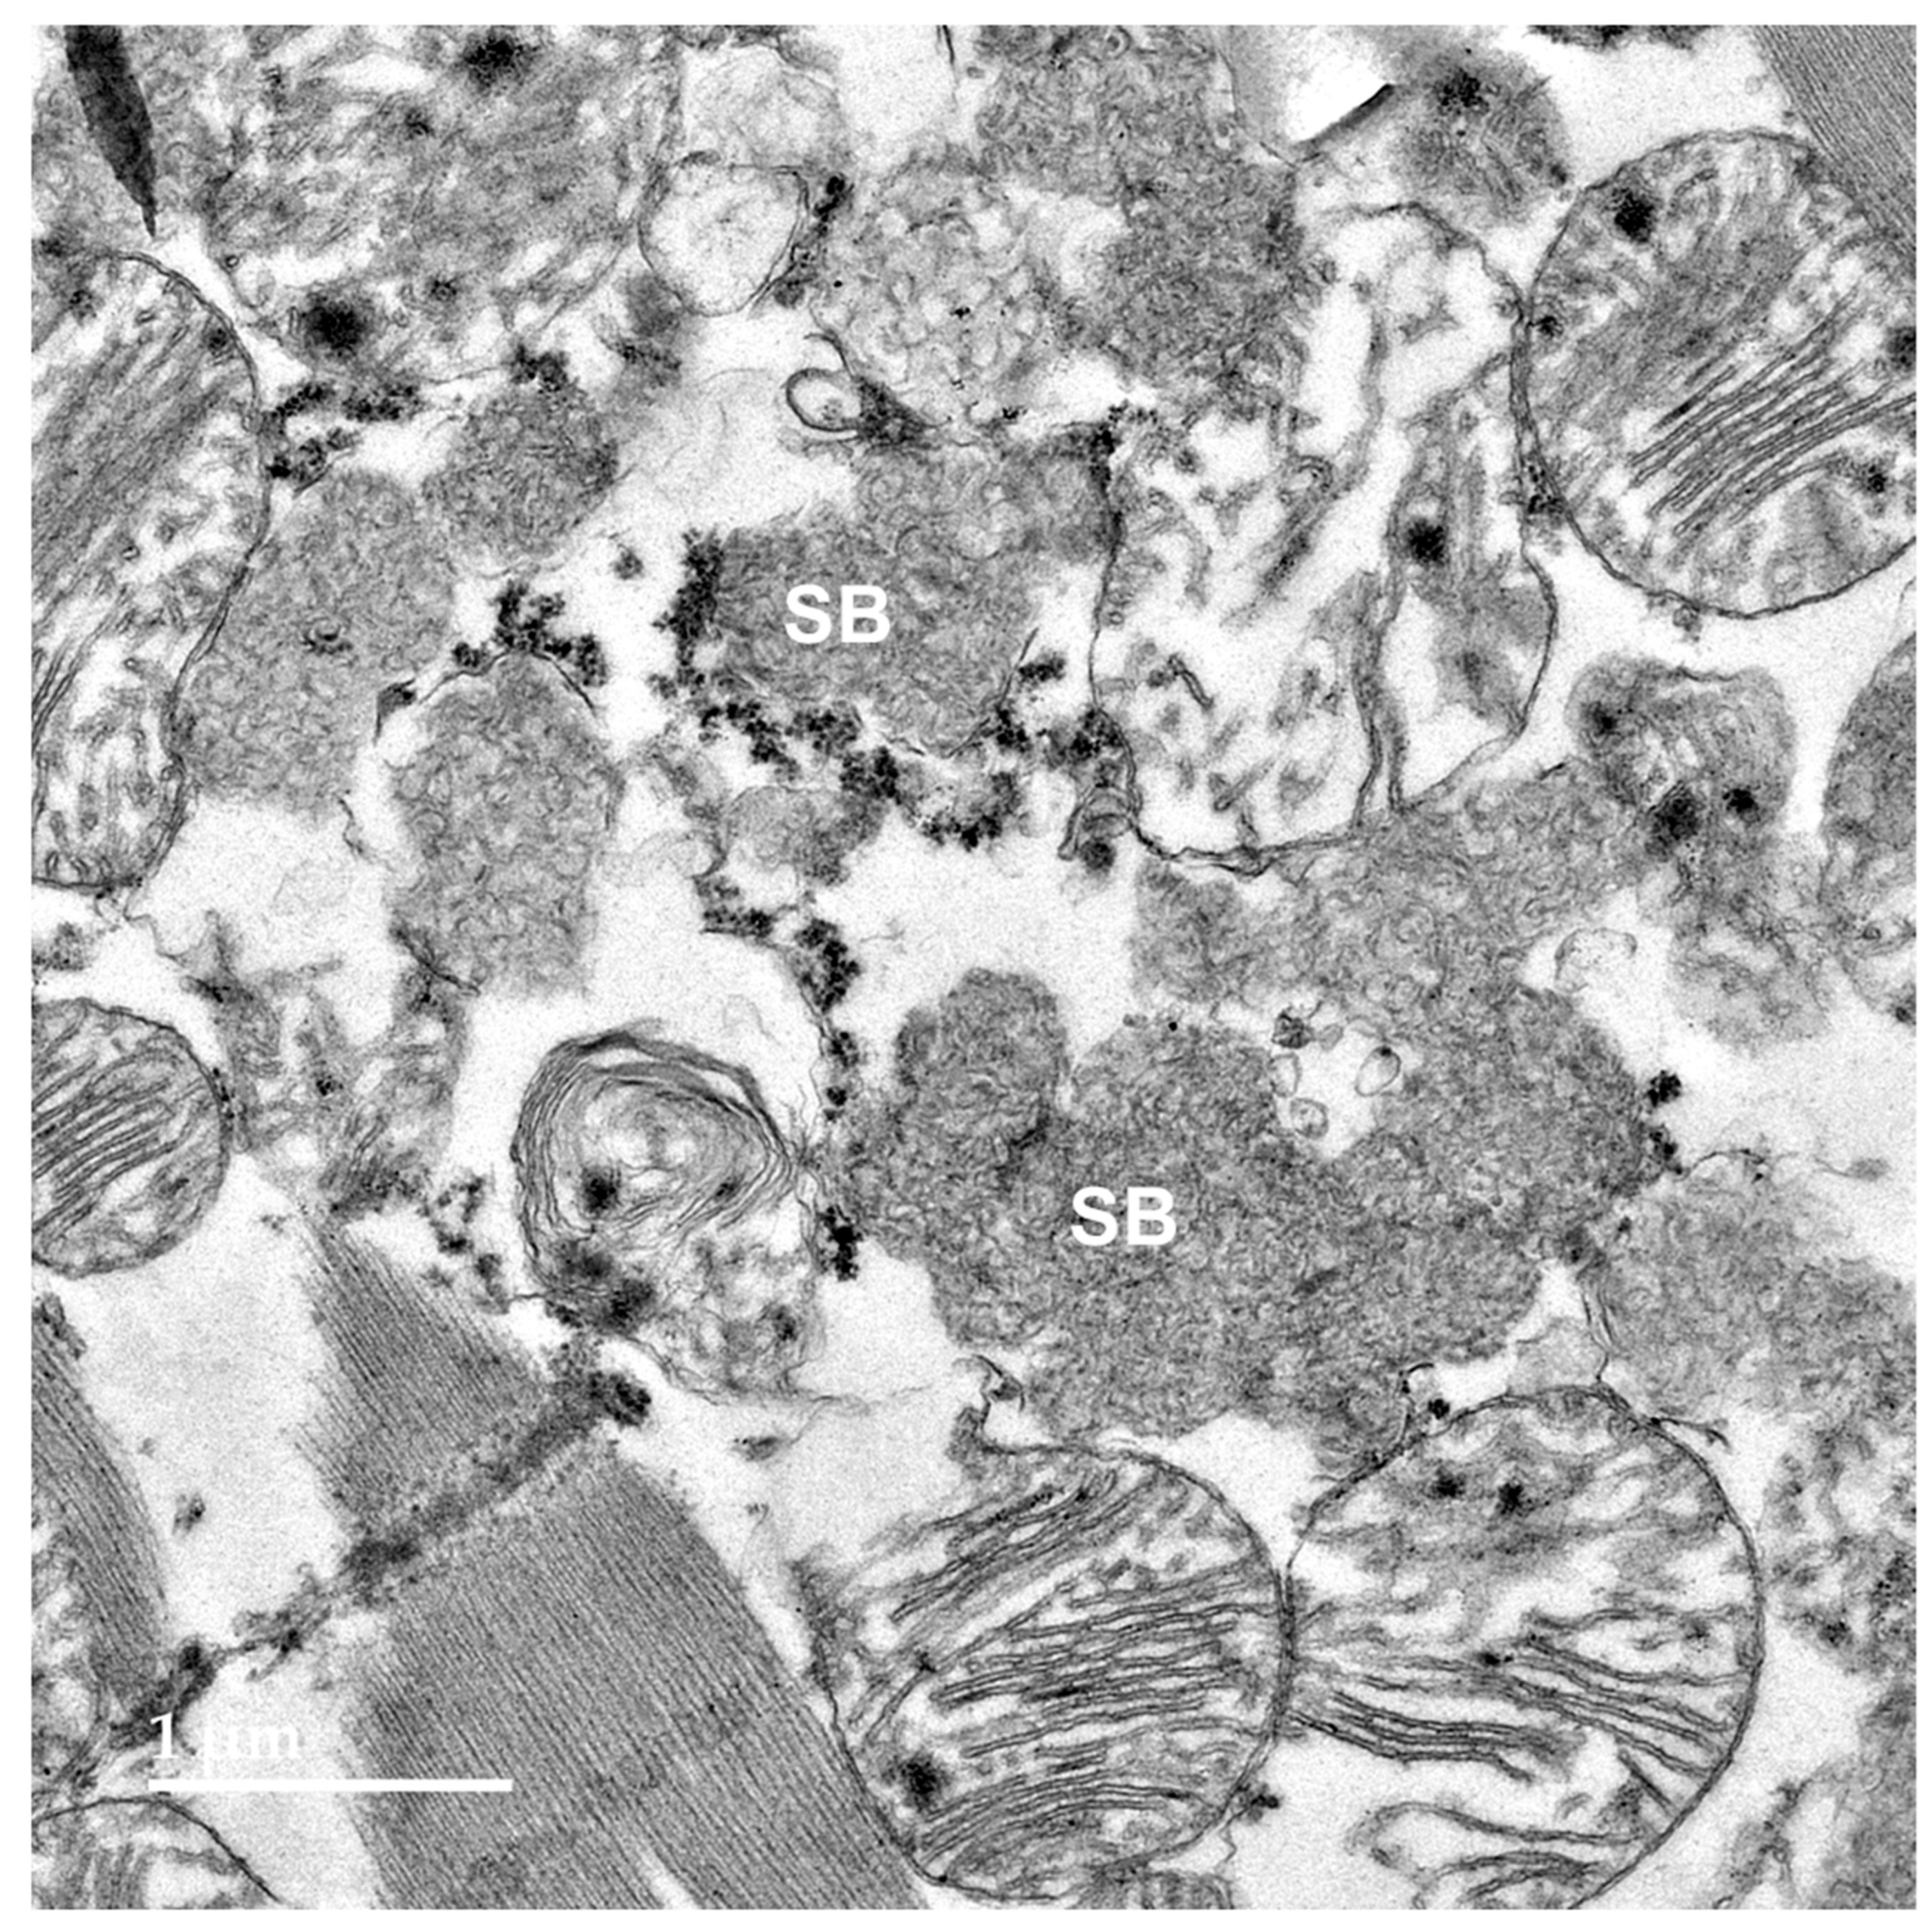

3.2. Microscopic Findings